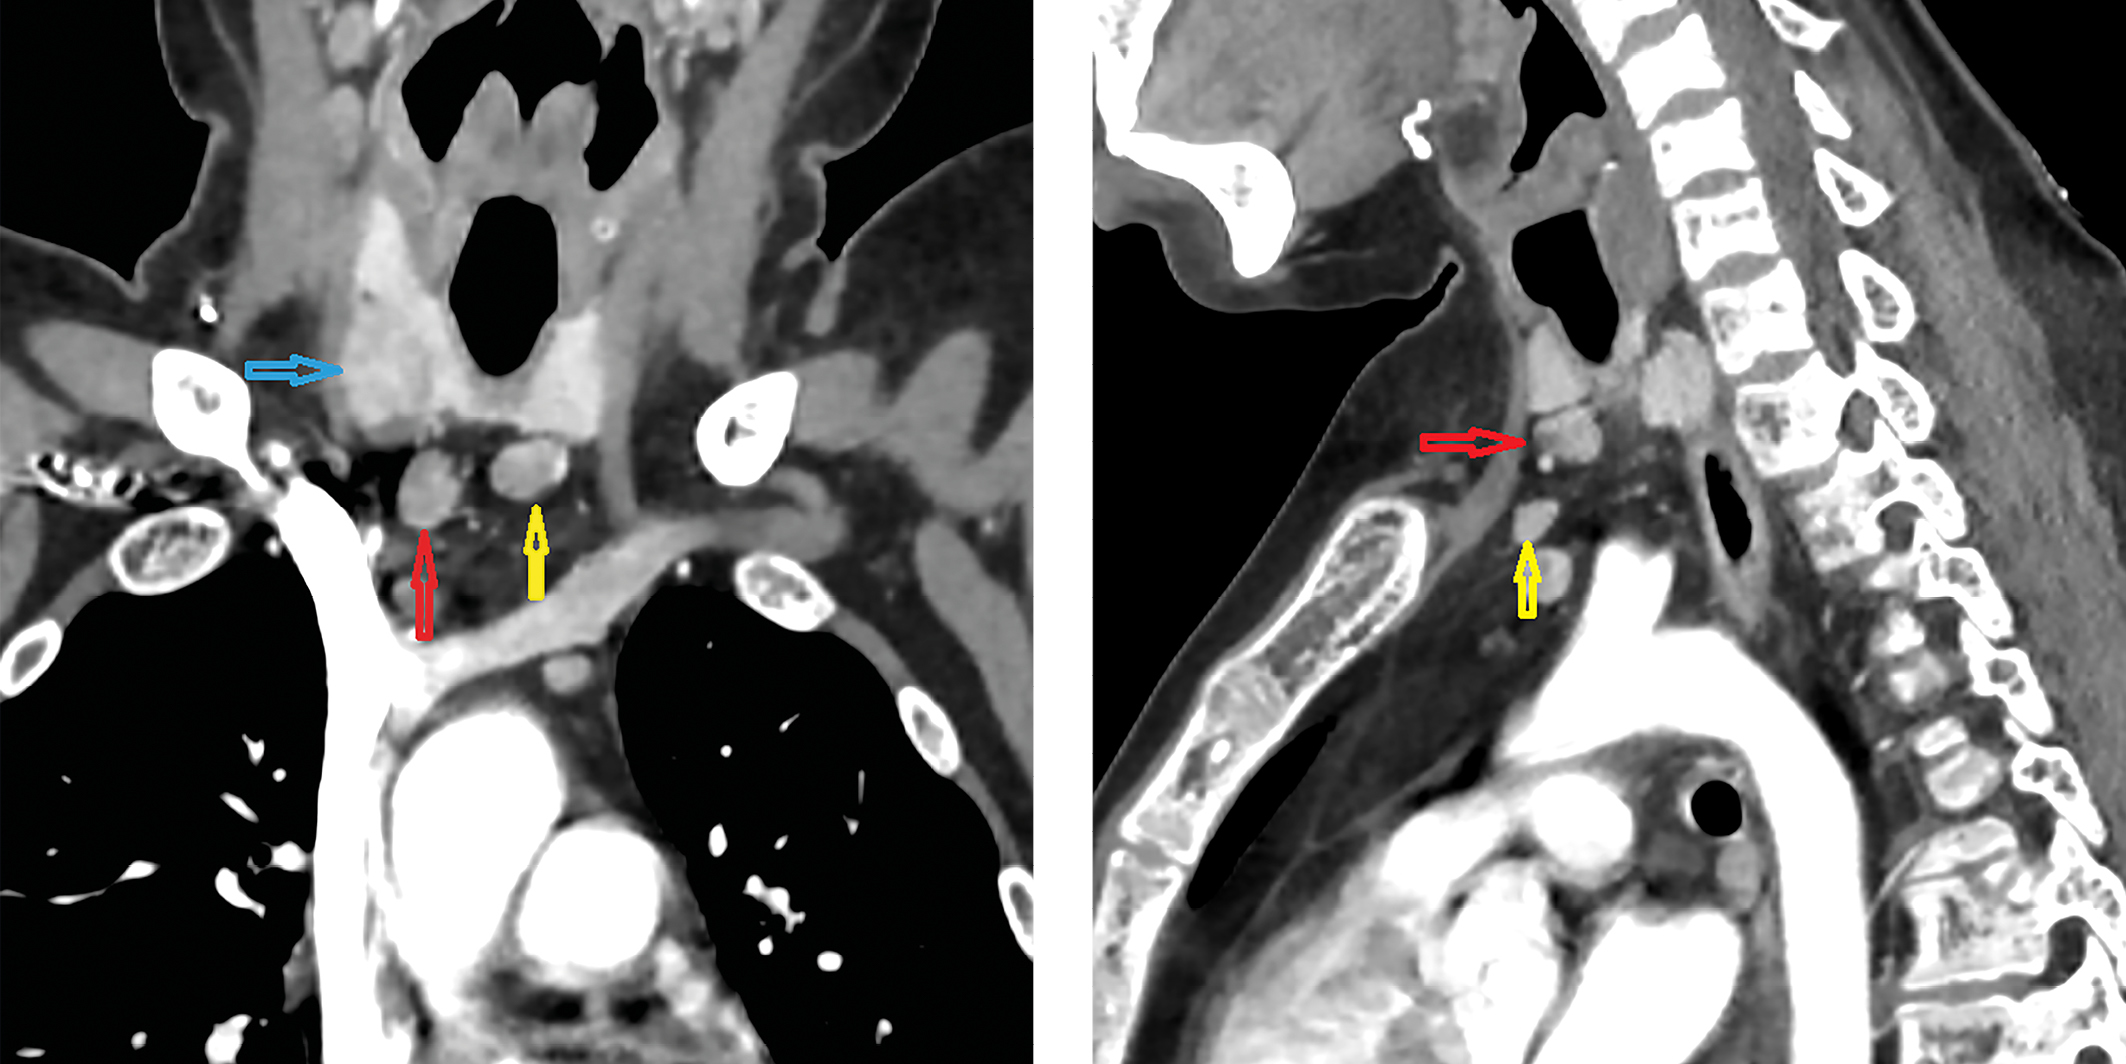

1. Рисунок 1. Мультиспиральная компьютерная томография шеи и верхнего средостения с внутривенным контрастированием (стрелками отмечены образования околощитовидных желез). | |